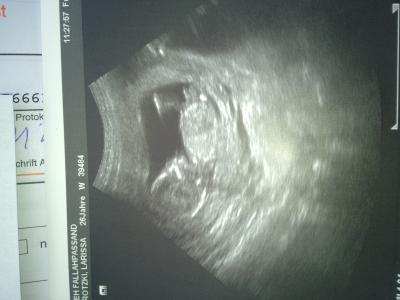

Hi Mädels hoffe es geht euch allen gut ???? Mir geht's ganz Oki im Moment wollte euch mal mein Krümmel zeigen Bild ist von Freitag 8.2.13

Bild zu Wollte euch mein Krümmel zeigen ;-) - Forum für August - Mamis

Sehr schönes Bildchen...sieht schon so groß aus!

ohhhhhhhhhhhhhh hallo du suesses fruechtchen...wie fein das bild ist. Ich will auch endlich wieder zum Scan...Maerz muss ma n bissl schneller kommen....